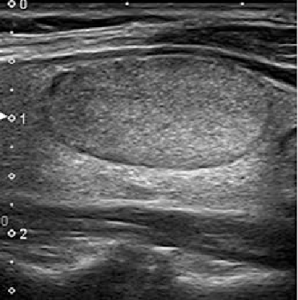

Tiroid üzerindeki bir hipoekoik nodül, bazen hipoekoik lezyon olarak adlandırılır, ultrasonda çevre dokudan daha koyu görünen bir kitledir. Bu genellikle, nodülün sıvı yerine katı bileşenlerle dolu olduğunu gösterir

Unutmayın ki, hipoekoik nodüllerin kanserli olma olasılığı daha yüksek olsa da, ekogenisite kendisi tiroid kanserinin güvenilir bir göstergesi değildir. Bu, sadece doktorunuzun biyopsi gibi ek testler yapması gerektiğinin bir işareti olabilir.